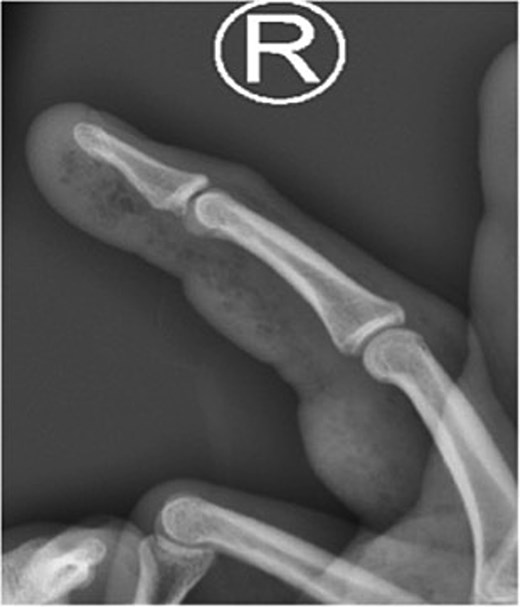

X-ray image of patient one showing injected material into volar surface of his digit.

X-ray image of patient three showing injected material into surface of his digit, more obvious in the proximal portion.